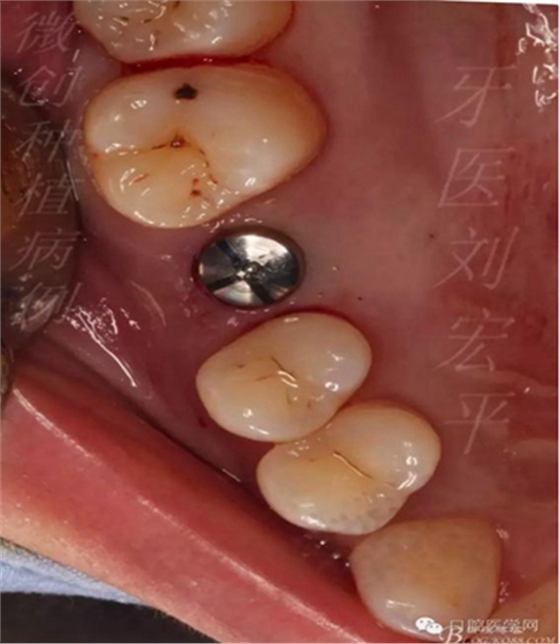

備洞植入,骨下1毫米

愈合基臺(tái)關(guān)閉傷口